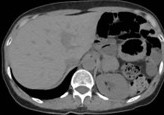

CT θώρακος-τραχήλου. Κόκκινα βέλη — Πολύ μεγάλη οπισθοστερνική βρογχοκήλη. Κίτρινα βέλη — Κλείδες (Ευγενική παραχώρηση Dr. V. Penopoulos)